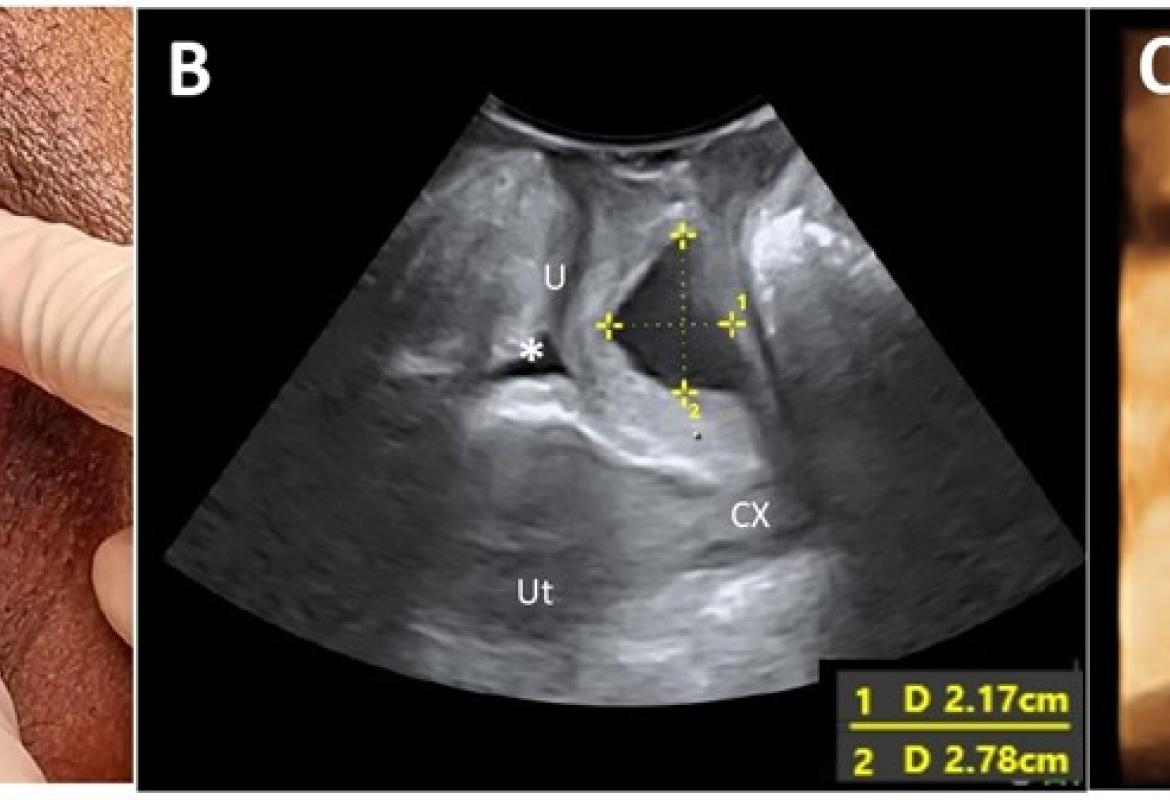

FIGURE 1: (A) A left periurethral mass extending from the left periurethral space to suburethral region measuring 3 cm x 5 cm; (B) Midsagittal view of the pelvic floor showing a cystic mass (*) dorsal to the urethra (U) measuring 2.17 cm x 2.78 cm on translabial perineal ultrasound (TPUS); (C) TPUS view demonstrating a periurethral mass dorsal to the urethra measuring 4.22 cm (width) x 1.99 cm (vertical dimension). (SP: Symphysis pubis; Ut: Uterus; CX: Cervix)